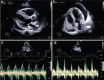

Acute pericarditis and cardiac tamponade after COVID-19 vaccination